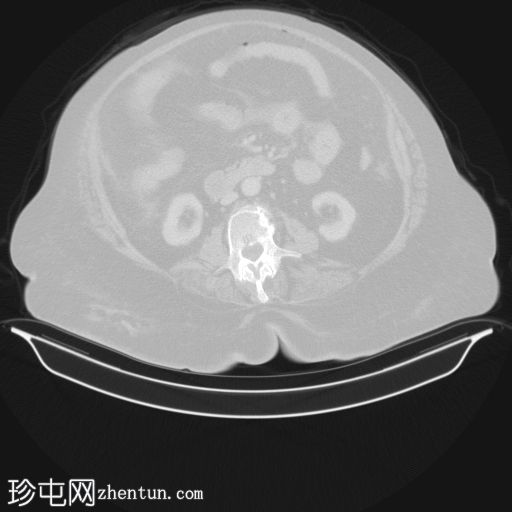

轴位增强扫描(门静脉期)

宫腔内可见气液平面,符合子宫蓄脓(宫腔内有脓液)。子宫前壁裂开,多个宫外气体灶延伸至腹膜外和腹膜内间隙,提示子宫穿孔。同时可见少量盆腔腹水和少量盆腔脂肪条索状改变。

其他发现:左侧附件囊肿、胆结石、双侧少量胸腔积液。